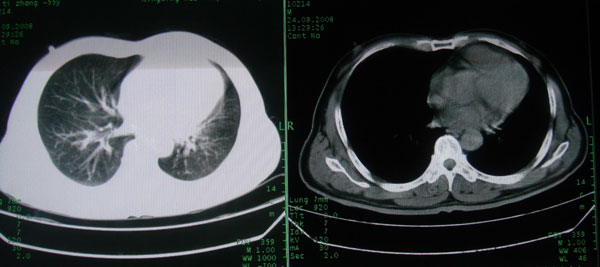

患者男性58岁因二周前起咳嗽,今天胸片示左上肺占位性病变行ct检查,无发热,无咯血痰.

左肺上叶病灶,实变但见含气支气管、空洞但未见壁内结节及积液;

考虑:①感染性病变(包括特殊感染型肺tb)

②肿瘤性病变(考虑患者年龄比较大的关系/所以不排除)

初学者。。。左肺空洞性病变,并可见阻塞性肺不张改变,鉴于患者为老年男性,且临床症状仅有咳嗽,全身中毒症状不明显,所以我首先考虑为左肺癌性空洞并左侧肺门淋巴结转移伴左肺阻塞性肺不张。结核性空洞放于第二位考虑,可以进行相关实验室检查。希望能有病理结果,谢谢!!!!!

左肺上叶实变影,内见支气管充气征及空洞影,病人年龄较大,无发热及结核中毒症状,心影左移,未见纵隔淋巴结肿大;不知实验室检查结果如何?有否嗜酸细胞增多,有没有进行治疗?就目前资料首先考虑1.感染性病变,2.慢性嗜酸性肺炎?可结合实验室检查并短期治疗复查,肺癌不能排除。